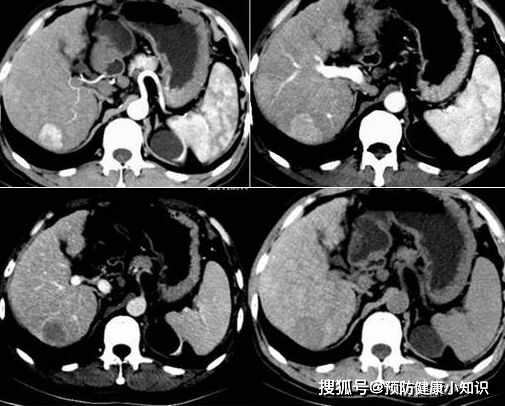

經過一系列檢查,小七被查出了肝癌,而且已經是晚期,癌細胞已經擴散,剛趕來的父母聽到以後,一下就癱坐在地上。

為什麼小七在沒有徵兆的情况下,會被查出肝癌?

因為肝臟屬於沒有感覺神經的器官,它發生病變的時候,早期的一些症狀很難被發現,即使被發現也很難引起重視。

肝臟作為我們的代謝器官,發生病變以後,膽紅素、毒素、雜質等不能被有效代謝分解,會淤積在皮膚,出現皮膚發黃、長痘、長斑的現象。

肝臟還是我們的合成器官,肝功能下降會導致膽鹼酯酶、膽汁等不能被合成,導致出現身體乏力、精神萎靡、消化不良的現象。

所以平時在出現這些早期症狀時,需要及時就醫檢查,並且通過合理治療、改善生活飲食,避免肝病持續惡化。